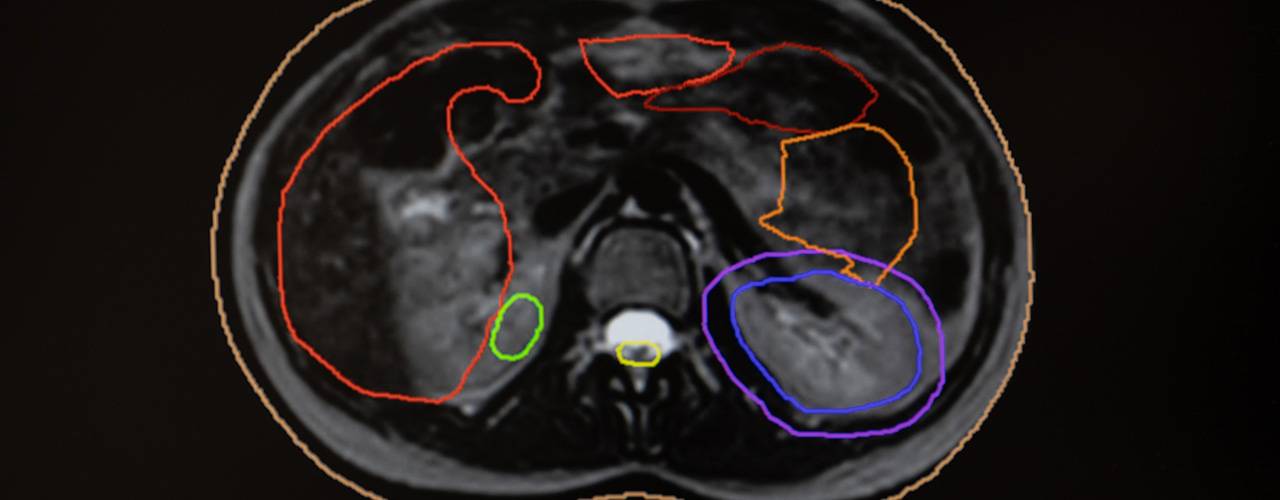

At present, in most hospitals, radiotherapy treatment planning is carried out using CT (computed tomography) images, but this is not very accurate when it comes to visualizing soft tissues and other areas, especially in the abdominal area. However, with the help of the MR Linac's 1.5 Tesla MRI, these tissues can be visualized with high clarity and definition.

During the sessions and over the duration of the treatment, the tumor shows changes in shape and position. The MR Linac technology allows real-time adaptive radiotherapy to be administered, which adapts the dose and precision of the radiotherapy administered to the patient according to the specific characteristics of each person and each tumor.

Integrated magnetic resonance imaging allows visualization of internal body movements, adjusting the dose or target of radiotherapy instantly.

High-quality images obtained in real time during treatment delivery minimize damage to surrounding healthy tissues.

One of the most difficult types of tumors to treat due to its location and proximity to vital organs is pancreatic cancer, which benefits significantly from MR Linac. The ability to adjust the treatment live as the tumor oscillates to the rhythm of internal body movements, such as breathing, allows for safer and more effective radiotherapy, minimizing the risk of damaging adjacent structures.